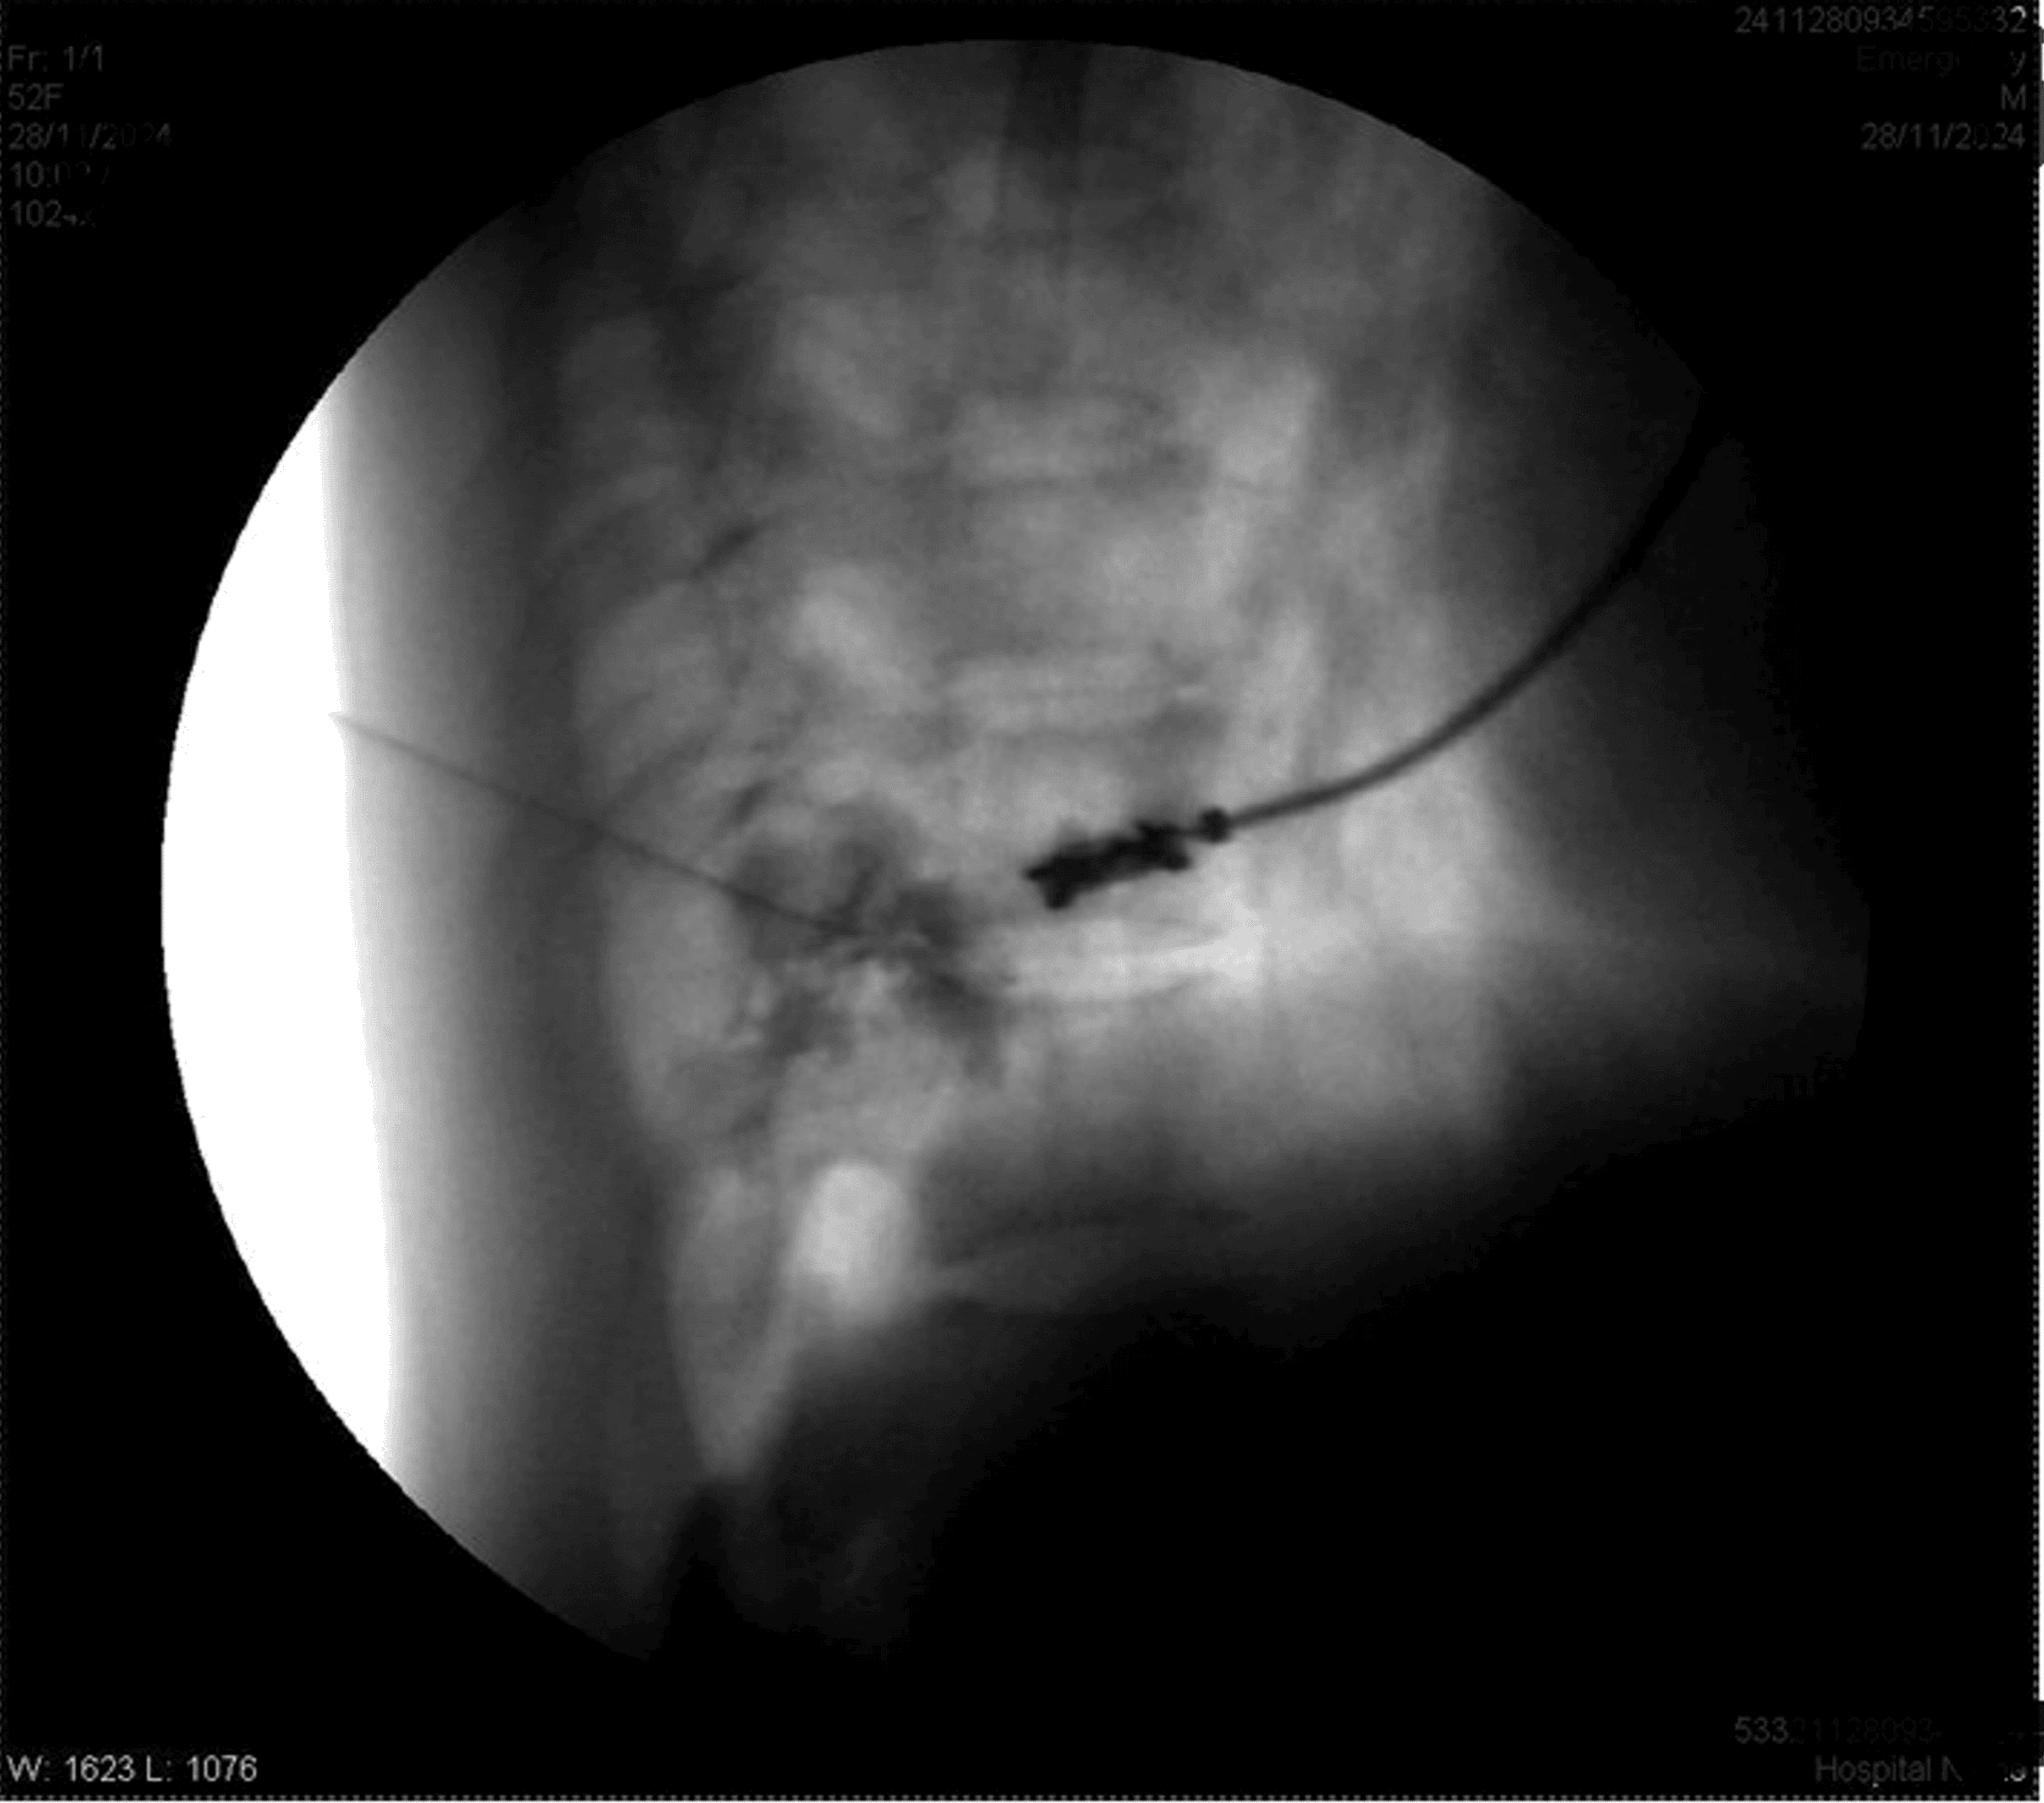

The patient was positioned prone. After painting and draping, the transverse process of T8 was located on the right side with the help of a C-arm. A Quincke needle (22 G) was inserted under fluoroscopic guidance to reach the transverse process of T8. The needle tip was advanced caudally along the transverse process until a loss of resistance was felt. The needle’s position was confirmed via fluoroscopy by injecting iohexol 300 radiocontrast dye, with images obtained in both anteroposterior and lateral views (Figures 1–4).